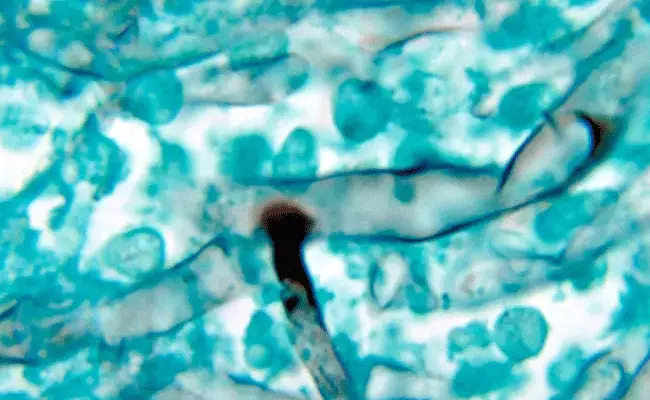

Black Fungus: భయపెడుతున్న బ్లాక్ ఫంగస్.. అసలేంటిది

Black Fungus: కరోనాకే కనికరం లేకుండా పోయిందనుకుంటే మరో కొత్త వైరస్ వచ్చి మరింత భయపెడుతోంది. దాని పేరు బ్లాక్ ఫంగస్ లేదా మ్యుకర్ మైకోసిస్ అని కూడా పిలుస్తున్నారు. మొన్నటి వరకు దేశ రాజధానికే పరిమితమైన ఈ వ్యాధి ఇప్పుడు తెలంగాణలో కూడా కనిపించడం కలకలం రేపుతోంది.